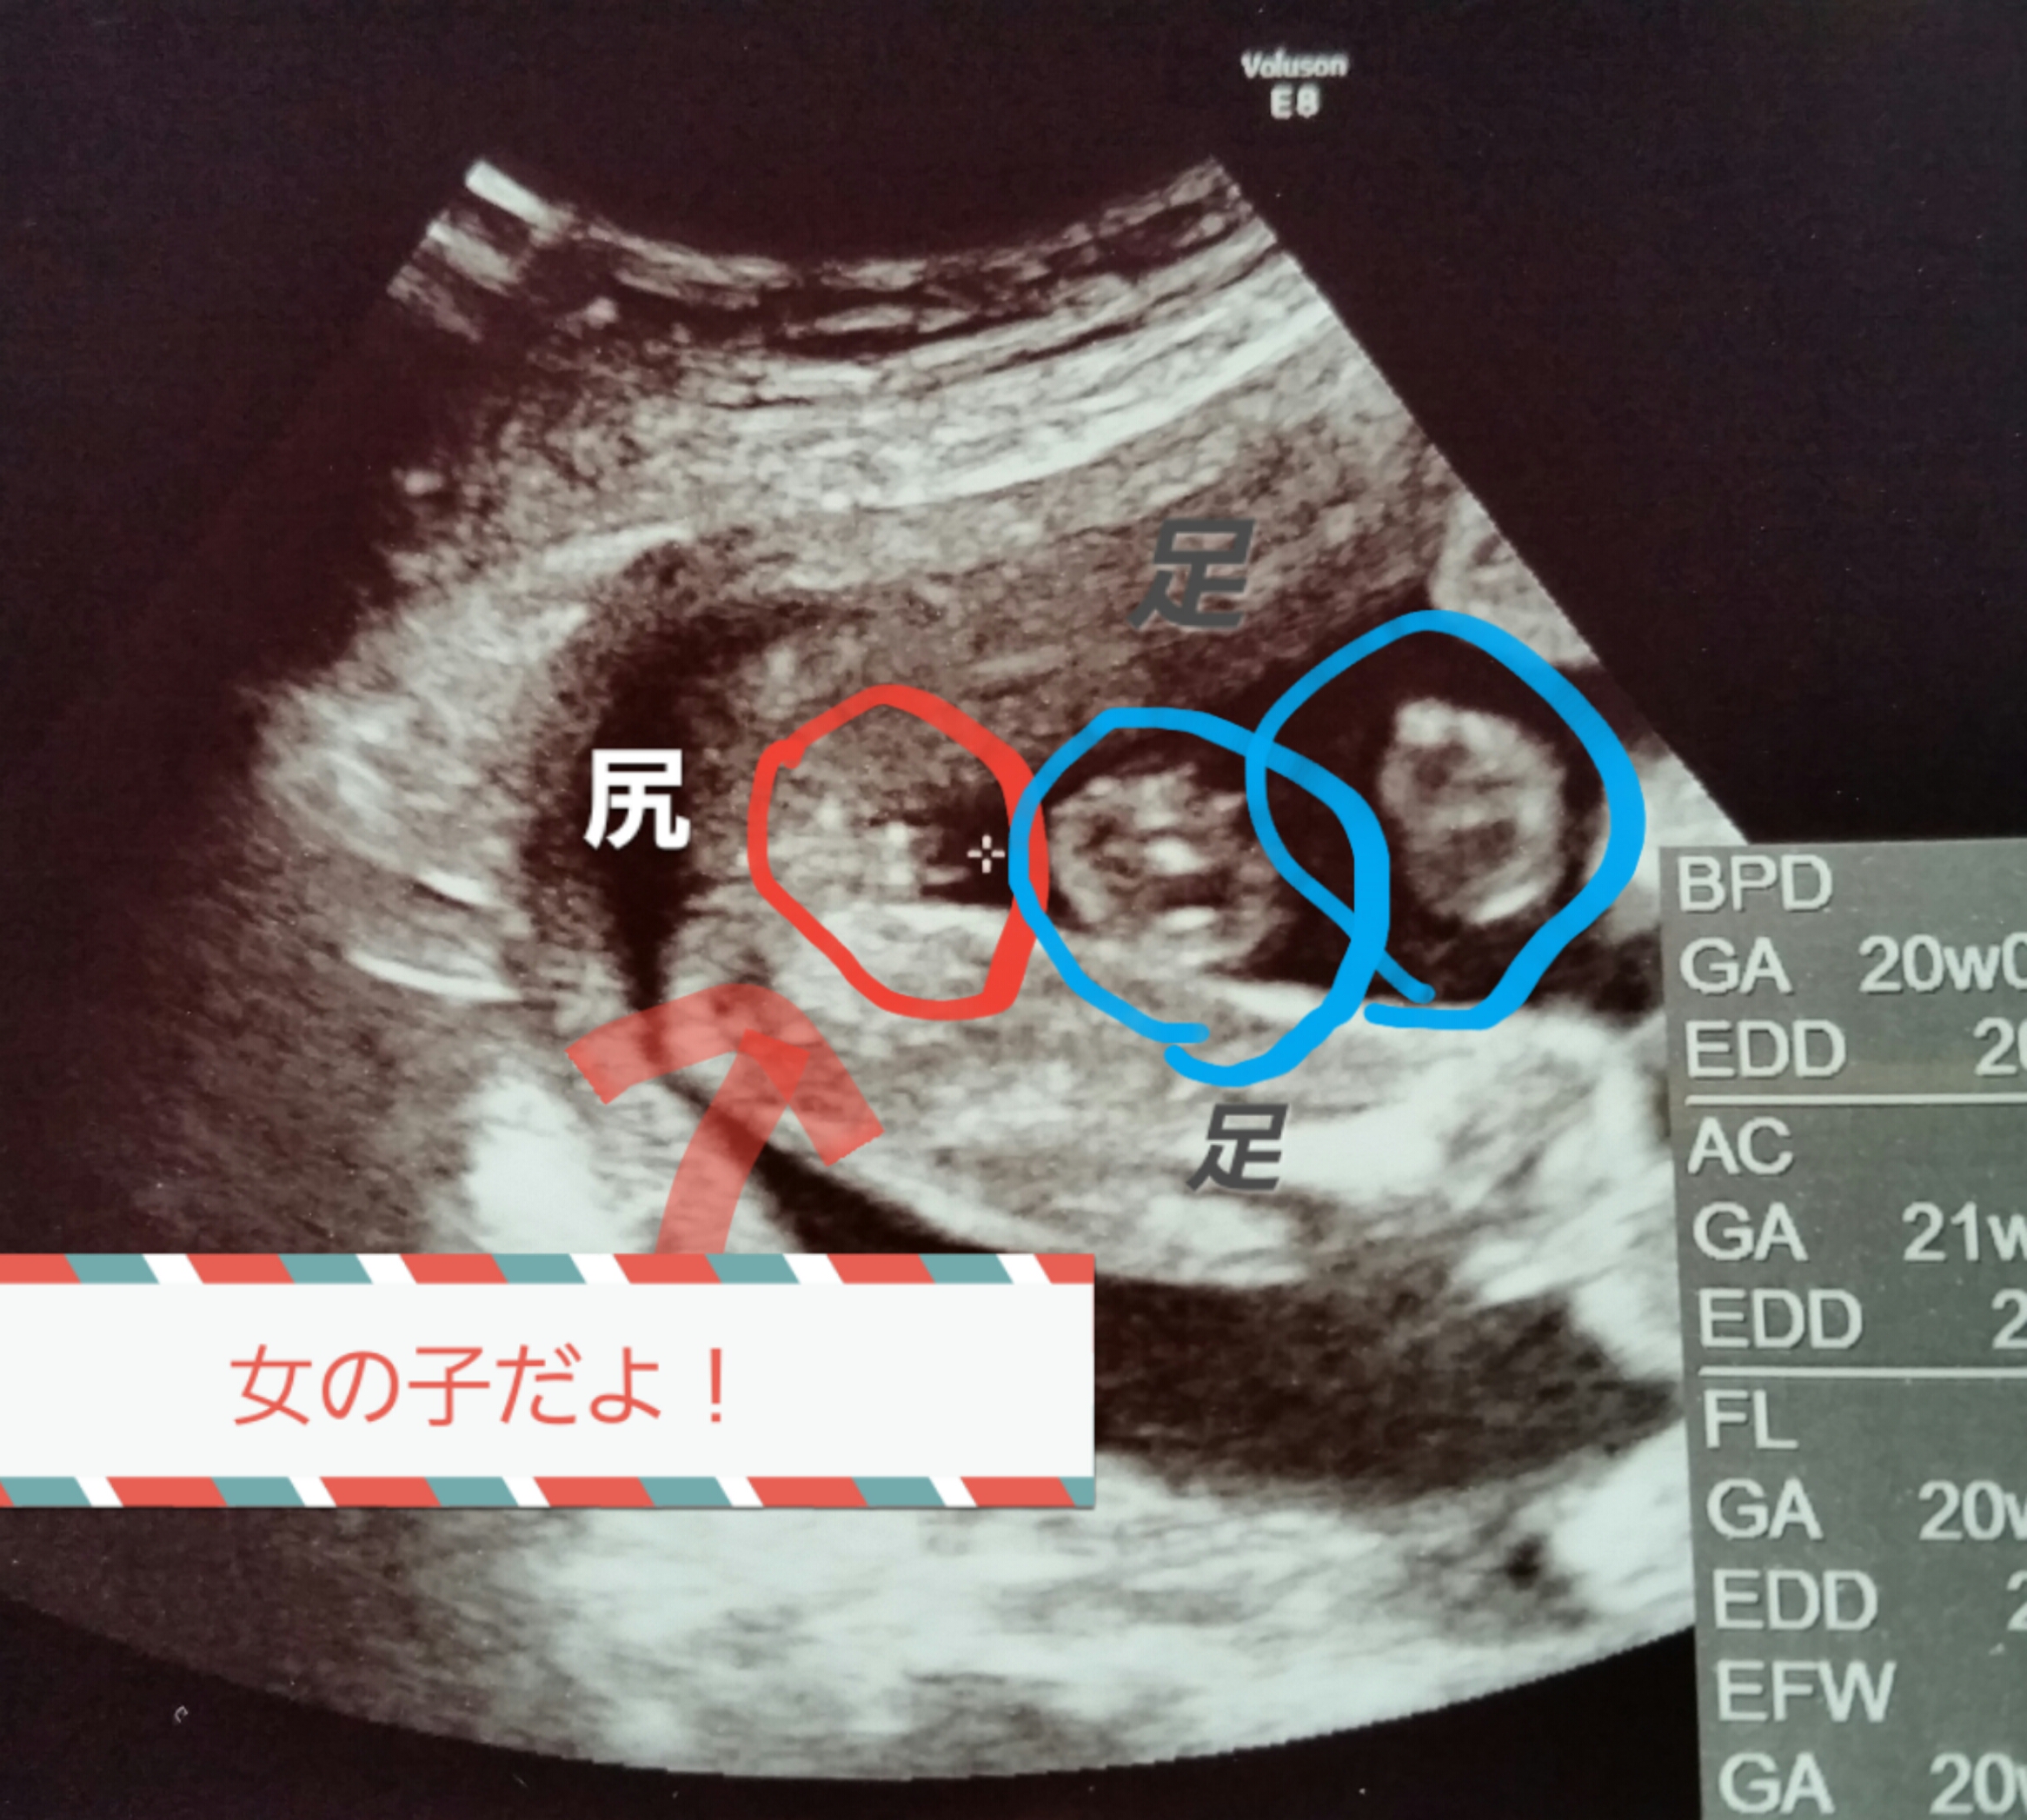

妊娠6ヶ月(20週・21週・22週・23週)の経過とエコー写真 20週3日(20w3d) 待ちに待った6ヶ月健診です。 20w3dの6ヶ月健診で性別が判明しました!!!!!!! ただ、この日は実はいつものエコーではなくて、4Dエコーを撮りました。. 性別が男の子から女の子に変わった先輩妊婦の体験談 体験談1 妊娠8ヶ月ごろに産婦人科の先生から「男の子で間違いないですよ」言われました。 私も確かにエコーで男の子の象徴をちゃんと見ました。. 今日で妊娠15週6日目、明日からは安定期と呼ばれる妊娠5ヶ月目に突入です。 もうね、最近本当にぐーたらした生活を送っておりまして(´ω`。)グスン ブログの更新どころか、仕事すら手についてないっていう。。。 つわりも落ち着いてきたのに、完全に堕落した生活を送っております。.

妊娠6ヶ月で性別判定出た エコー写真で見る女の子の図 Mamaにゃ ごの育児生活ブログ

女の子のエコー写真 6ヶ月の頃 Nikomame ニコマメ